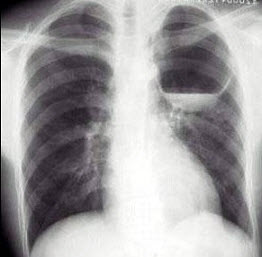

24、单项选择题

男,22岁,感胸痛且大汗淋漓就诊,X线检查如图,最可能的诊断是()